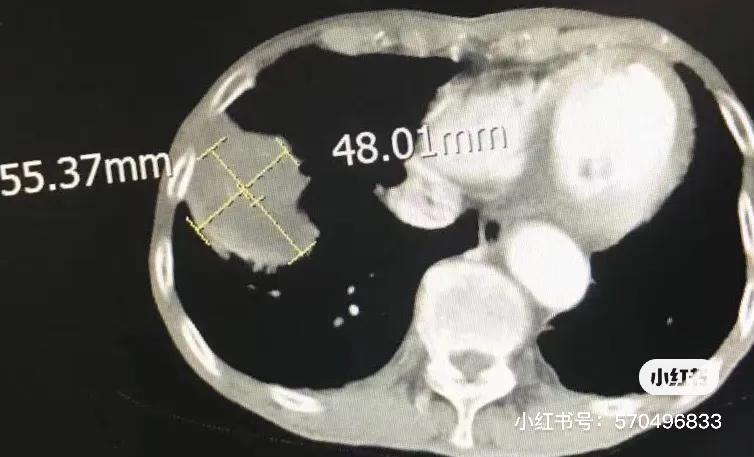

第一次冷冻后一个月CT